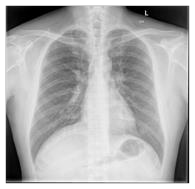

Recent advances in general medical AI have made significant strides, but existing models often lack the reasoning capabilities needed for complex medical decision-making. This paper presents GMAI-VL-R1, a multimodal medical reasoning model enhanced by reinforcement learning (RL) to improve its reasoning abilities. Through iterative training, GMAI-VL-R1 optimizes decision-making, significantly boosting diagnostic accuracy and clinical support. We also develop a reasoning data synthesis method, generating step-by-step reasoning data via rejection sampling, which further enhances the model's generalization. Experimental results show that after RL training, GMAI-VL-R1 excels in tasks such as medical image diagnosis and visual question answering. While the model demonstrates basic memorization with supervised fine-tuning, RL is crucial for true generalization. Our work establishes new evaluation benchmarks and paves the way for future advancements in medical reasoning models. Code, data, and model will be released at \href{https://github.com/uni-medical/GMAI-VL-R1}{this link}.